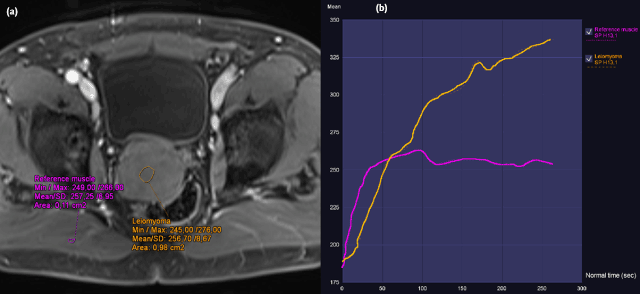

Figure 3

a) DCE (75 sec) and b) DCE curve. Transverse T1 vibe pre and post intravenous contrast showed homogeneous contrast uptake. The lesion showed slow first pass and progressive enhancement in second pass, the reference muscle (right sides musculus gluteus maximus) showed a slow first pass and a plateau in second pass.